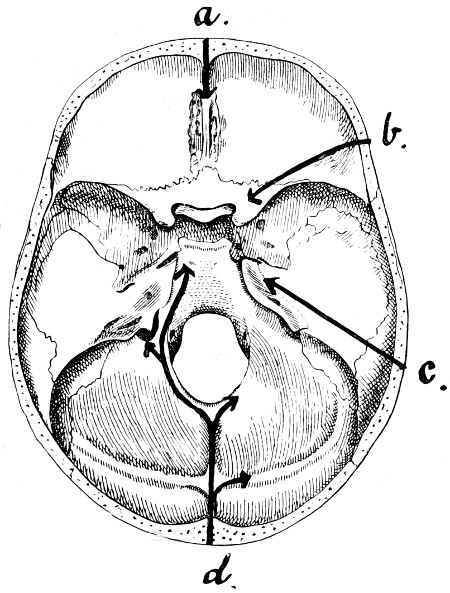

| 30. Plan of the base of the skull | 77 |

| 50 A and B. The inner aspect of the skull and the same seen on transillumination | 137 |

| 51. To illustrate compression of the brain as produced by an extra-dural hæmorrhage from the middle meningeal artery[x] | 141 |

| 52 A and B. The operative treatment of middle meningeal hæmorrhage | 144, 145 |

| 53. A basic fracture with laceration of both carotid arteries | 148 |

| 54. A basic fracture with laceration of the cavernous sinus | 149 |

| 55. A basic fracture with laceration of both lateral sinuses | 151 |

| 56 A and B. The operative treatment of subdural hæmorrhage | 156, 157 |